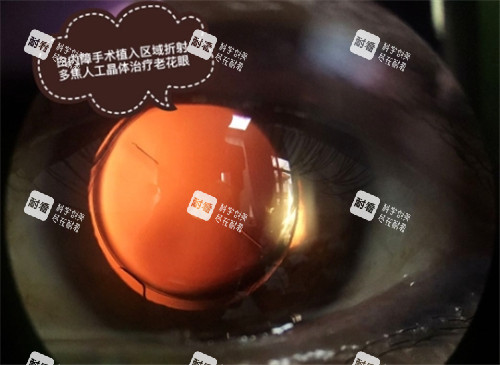

现代白内障手术已经取得了长足进步。主流的超声乳化白内障手术在眼部表面麻醉或局部麻醉下进行,医生在显微镜下于角巩缘或角膜缘做1.8~3.5毫米的微小切口,然后圆形撕囊,用超声乳化将患者的白内障打成乳糜状并吸出,再植入折叠好的人工晶体。

这种手术方式具有多重优势:切口小,不需要缝线关闭切口而只需用水密闭伤口,降低了手术引起散光的风险;手术时间短,术后改善快,多数患者不需要住院或仅住院1天。

更为靠前的是飞秒激光辅助白内障手术,如陈多多婆婆所接受的手术类型。飞秒激光技术进一步提高了手术的精细度和安心性,通过激光完成切口制作、撕囊等关键步骤,减少超声能量的使用,为患者带来更好的术后结果。

手术过程中,医生会摘除已经混浊的晶状体,并植入适当度数的人工晶状体,使光线能够正常聚焦在视网膜上,从而改善视力。这一过程看似简单,实则要求医生具备精细的操作技巧和丰富的临床经验。